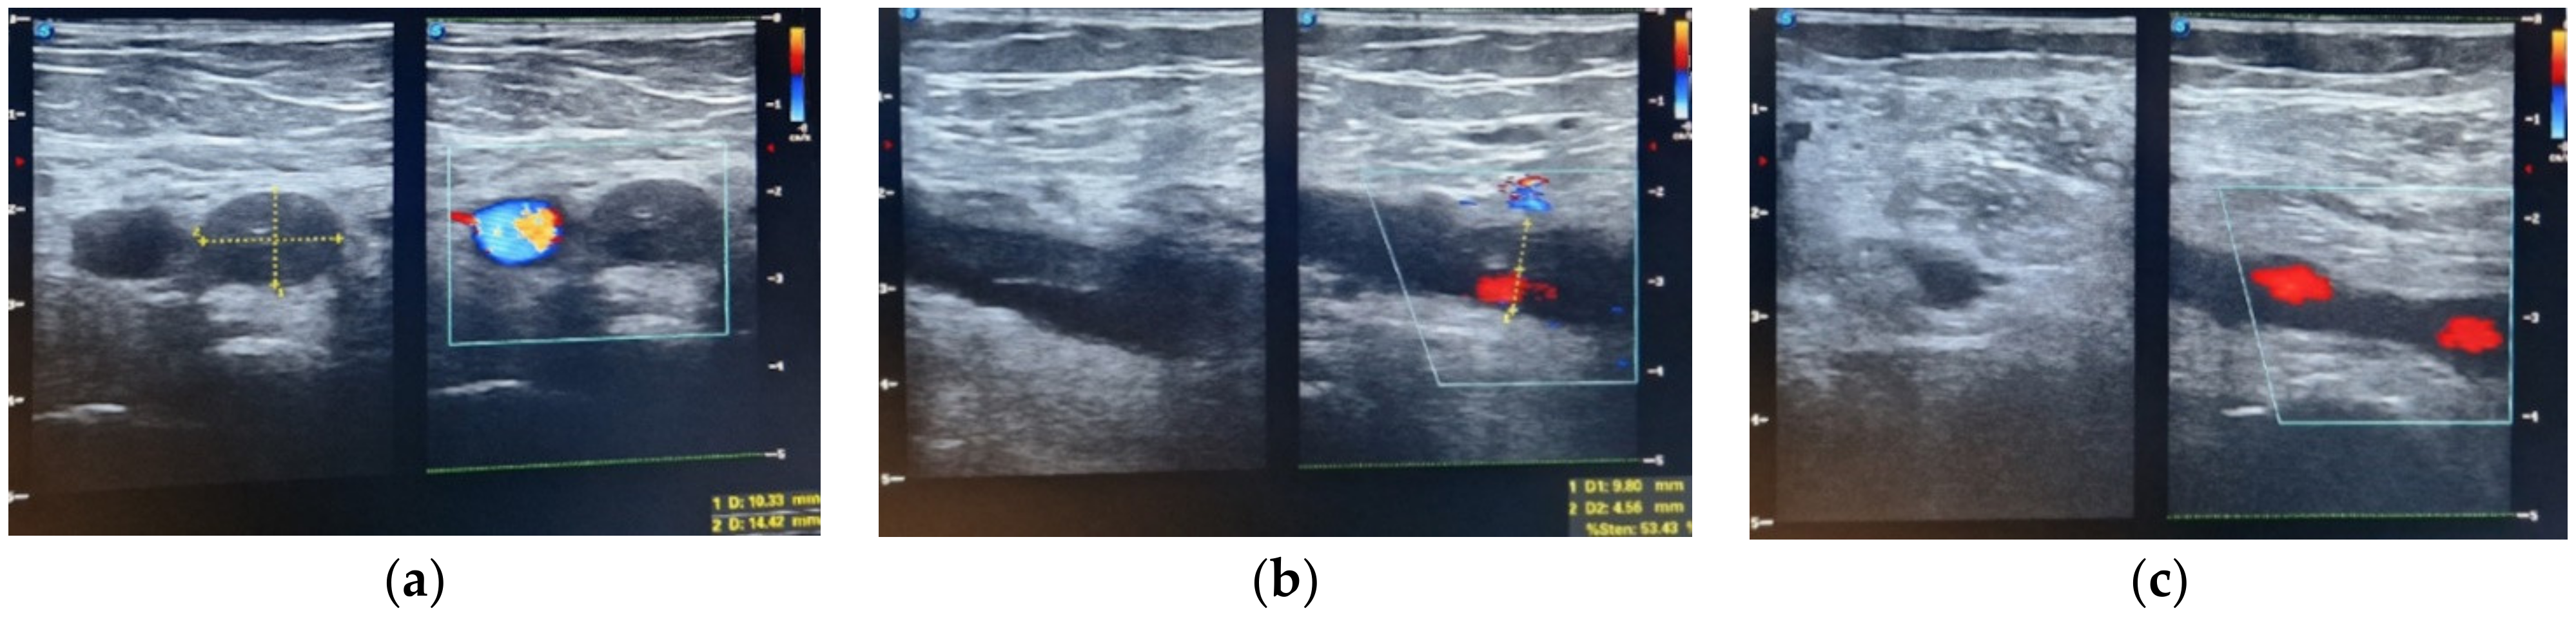

Figure 2. Duplex ultrasonography (a) iliac vein thrombosis, (b) femoral vein thrombosis, (c) popliteal vein thrombosis in resolution (day 25 after thrombosis).

Out of the 13 patients, 10 patients had symptomatic DVT (2.02% of the total patients included in the study), characterized by unilateral swelling of the limb, with tenderness or pain. We registered one case of deep vein thrombosis at the level of the upper limb; in the remaining nine cases, the lower limb was affected. Duplex ultrasound was used to diagnose DVT and the entire venous system of the affected extremity was assessed for compressibility, augmentation, and intraluminal echoes. A duplex ultrasound was also performed on the contralateral limb, but we did not detect any bilateral lower extremity thrombosis. At the moment of diagnosis of venous thromboembolism, the mean level of D-dimers was 1627.66 ng/mL. Serial ultrasound examinations were conducted weekly to monitor the size and evolution of the thrombus under treatment.

The average ABSI score was 8 points. The average TBSA was 30.38%, with TBSA between 1% and 75% TBSA. The patient with 1% TBSA had a femoral venous catheter placed on the limb affected by deep vein thrombosis, and the Caprini score was 14. The patient was obese, suffered from diabetes and hypertension, and had a history of cervical cancer 3 years before the burn injury, treated by total hysterectomy and bilateral adnexectomy, external beam radiation therapy, and brachytherapy (Figure 2 and Figure 3). The patient with 4% TBSA had DVT on the donor limb for split-thickness skin grafts. The Caprini score was 14, the patient was obese and suffered from VHB/VHC co-infection, liver cirrhosis, hepatocarcinoma stage IV (lung and bone metastases), and followed a chemotherapy regimen.